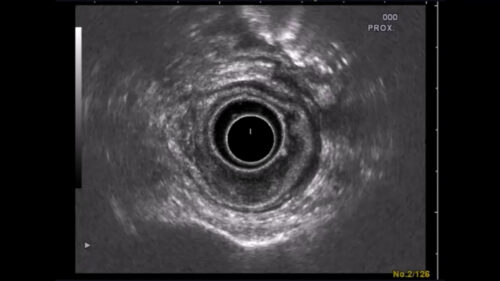

Endosonografiebeispiel

Bei diesem Patienten liegt ein lokal fortgeschrittenes Rektumkarzinom im Stadium uT3 uN+ vor. In der Endosonografie kann man die normale 5-Schichtung des Rektums sehen, die aus den Wandschichten und den sonografischen Grenzflächen besteht. Bei 5-6 Uhr SSL ist eine Raumforderung zu erkennen, die diese Wandschichtung aufhebt. Gut zu sehen ist, wie die äußere echoarme Schicht, die die Serosa repräsentiert, durchbrochen wird.

Endosonografie

In der Endosonografie kann man besonders gut die Ausbreitung des Tumors über die Wanschichten des Rektums sehen. Normalerweise sieht man fünf Sichten in der Sonografie, den Wandschichten des Rektums entsprechend incl. der sonografischen Grenzschichten. Auch vergrößerte Lymphknoten sind leicht zu erkennen, wobei dies über die Dignität natürlich nichts aussagt. Auch entzündliche Lymphknoten sind vergrößert, vor allem einige Tage nach einer Biopsie. Dennoch ist jeder vergrößerte LK verdächtig auf eine Metastase und wird dementsprechend als uN+ gewertet. Tumor uT3 Lymphknoten uN+Einteilung